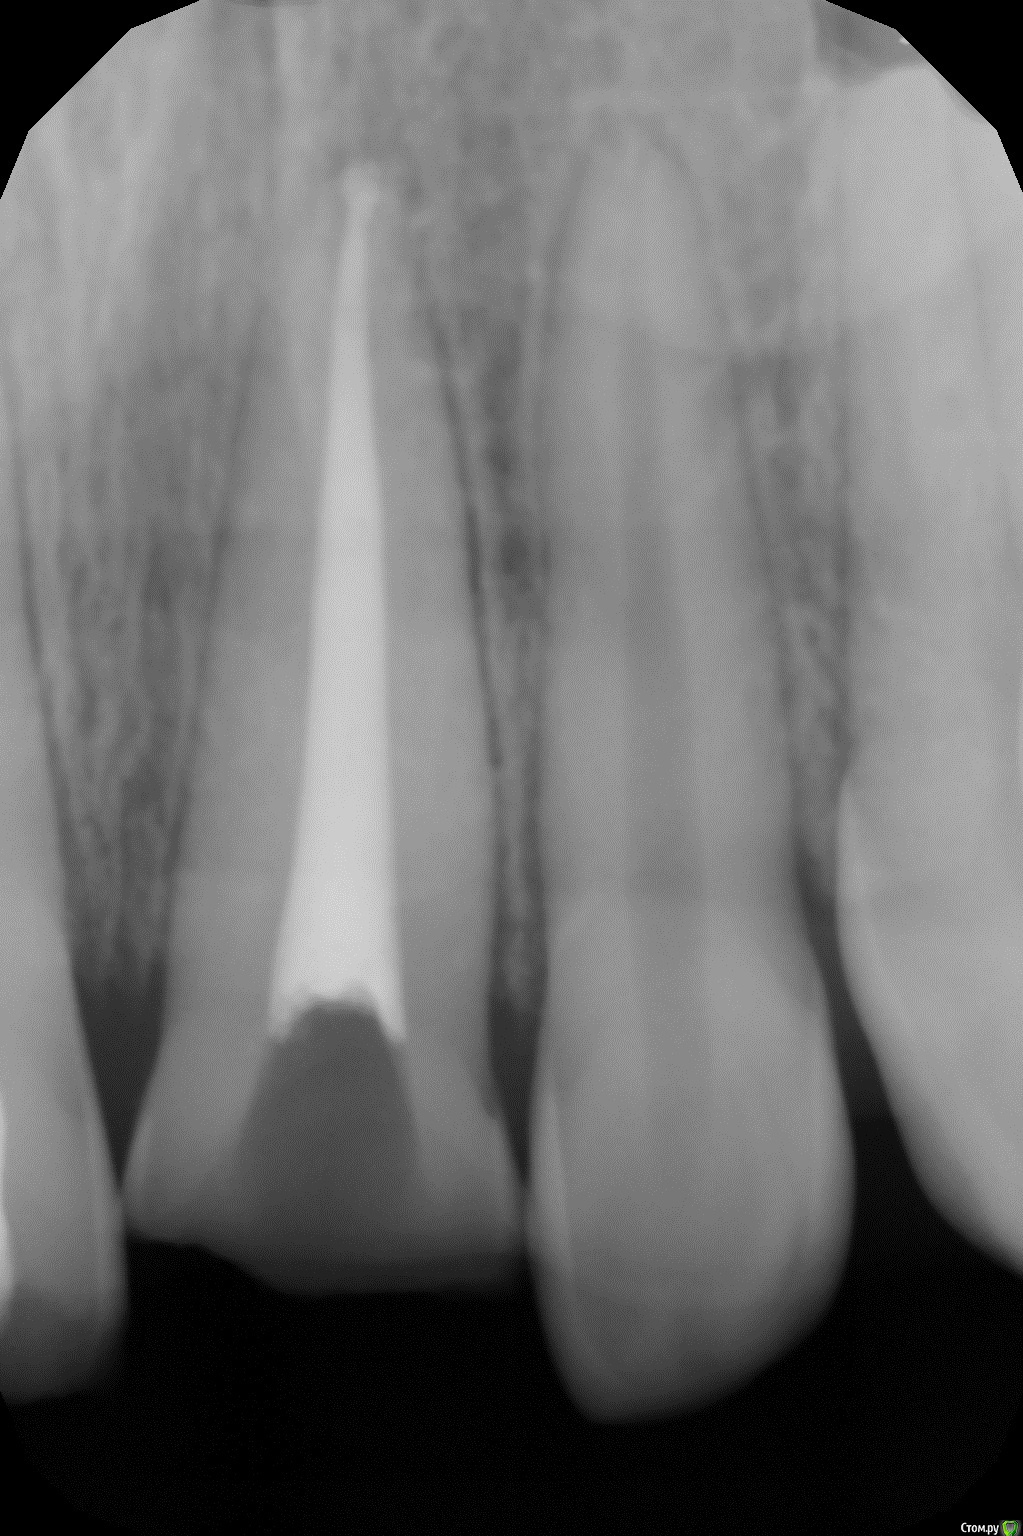

Art 7 Опубликовано 11 августа, 2017 Поделиться Опубликовано 11 августа, 2017 ставишь стекловолоконную балку между апроксимальных поверхностях соседних зубов) Ссылка на комментарий

kamranchick Опубликовано 11 августа, 2017 Автор Поделиться Опубликовано 11 августа, 2017 ставишь стекловолоконную балку между апроксимальных поверхностях соседних зубов)Спасибо Артурчик)Попробуем так))) просто шатается сильно, страшно трогать пока что) Ссылка на комментарий

kamranchick Опубликовано 11 августа, 2017 Автор Поделиться Опубликовано 11 августа, 2017 Это обычная силиконовая каппа ?вытягиваем, потом стабилизация ? Как на долго?капу сделали вакуум формером, помоему она пластмассовая вроде. стабилизация 2-3 месяца... Ссылка на комментарий